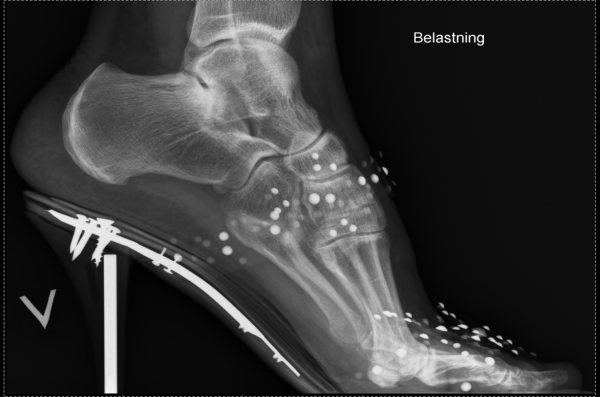

Høyhælte sko gir uheldig belastning på forfoten og kan føre til kroniske smerter i tærne. (Foto: St.Olavs Hospital)